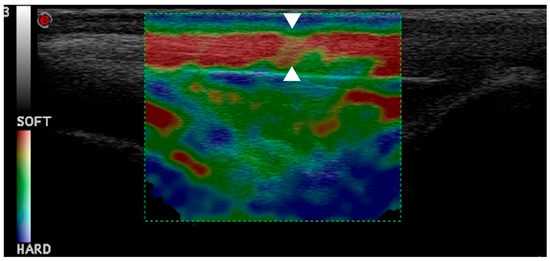

2.4. Ultrasonographic and Strain Elastosonographic Evaluations

3.3. Strain Elastosonographic Evaluation

- Pennasilico, L.; Volta, A.; Sassaroli, S.; Di Bella, C.; Riccio, V.; Pilati, N.; Tambella, A.M.; Dini, F.; Palumbo Piccionello, A. Ultrasound and elastosonographic features of the patellar ligament in dogs affected by cranial cruciate ligament disease. Vet. Sci. 2024, 11, 126. [Google Scholar] [CrossRef]

- Palumbo Piccionello, A.; Serrani, D.; Busoni, V.; Salvaggio, A.; Bonazzi, M.; Bergamino, C.; Volta, A. Sonoelastographic features of the patellar ligament in clinically normal dogs. Vet. Comp. Orthop. Traumatol. 2018, 31, 279–284. [Google Scholar] [CrossRef]